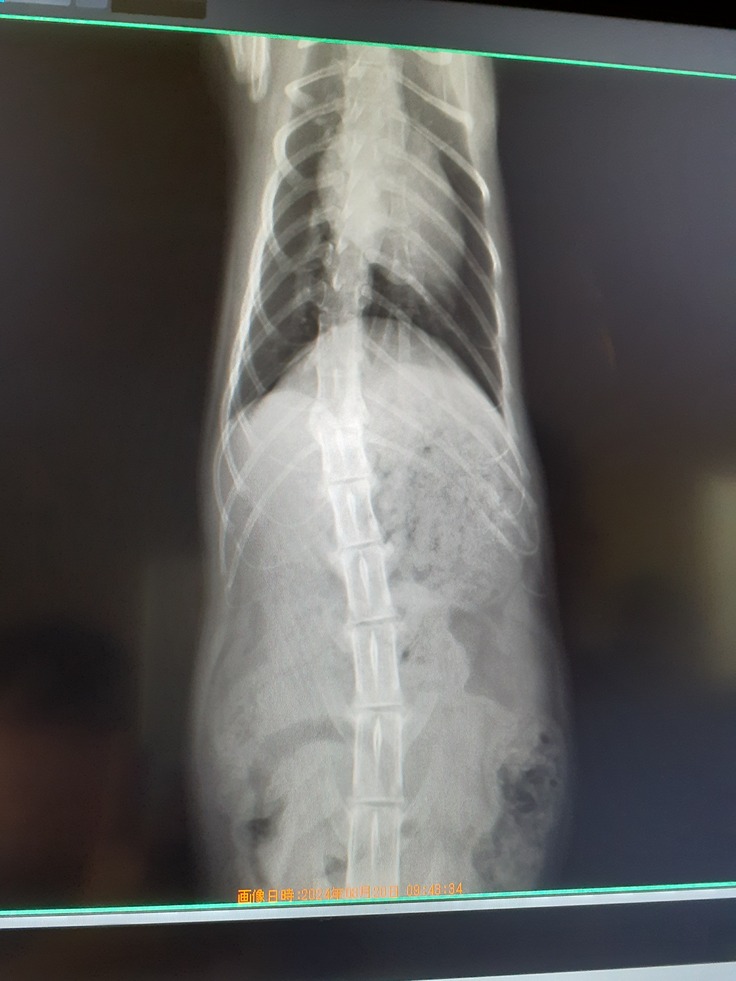

その足で動物病院にてウイルス検査、レントゲン、血液検査、便検査をしました。

レントゲンはやはり骨折。胸椎12番目が骨折をしていました。

普通に骨折ならまだ可能性はありましたが下に折れて、ズレていますのでちょっと厳しいかなと思っています。

もう固まってしまっているので元には戻らないですがそれでも希望を持って譲り受けた補助器で少しでも踏ん張る力を養えれればなと思います。